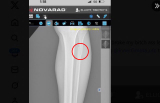

- エリオットのレントゲン写真(@TElliott125より)

- すねがポッキリと折れている(@TElliott125より)